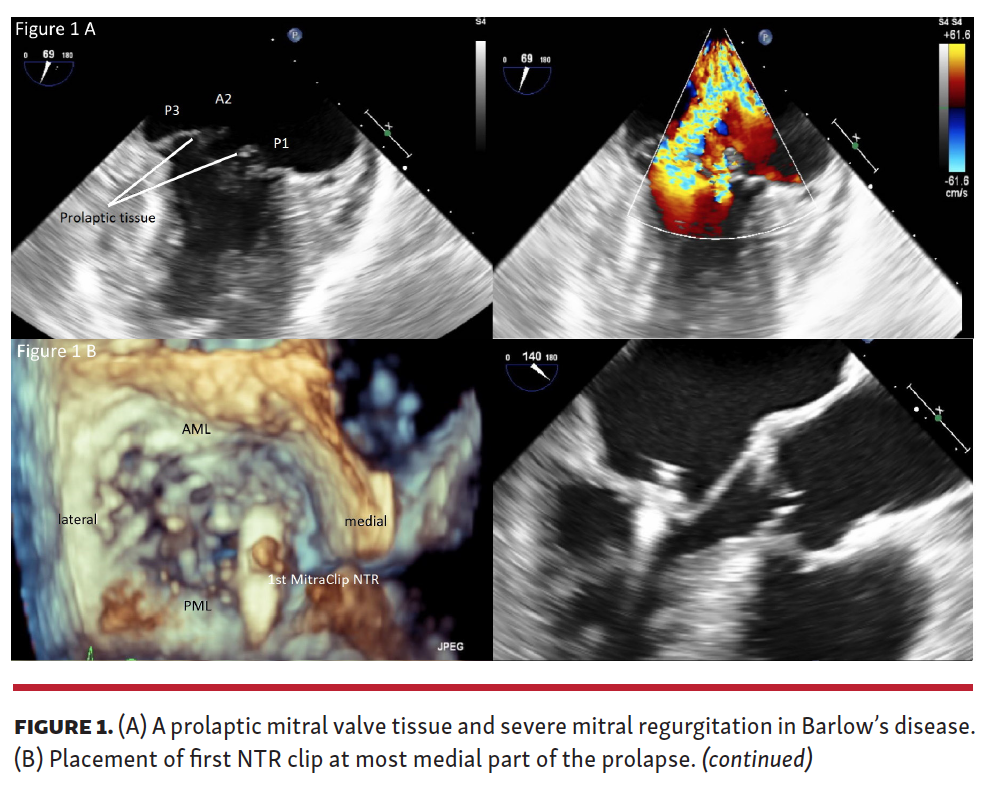

Patient with primary MR with typical features of Barlow's disease

Treating Mitral Valve Prolapse in Barlow’s Disease by Creation of a Barlow Type Mitral Valve According to the cleveland clinic, barlow’s mitral valve disease is a degenerative mitral valve. What is barlow’s mitral valve disease? Degenerative mitral valve disease causing mitral valve prolapse is the most common cause of primary mitral regurgitation,. Mitral valve prolapse is a condition where the one or two of the leaflets of the mitral valve become floppy and instead of. Barlow Type Mitral Valve.

Treating Mitral Valve Prolapse in Barlow’s Disease by Creation of a Barlow Type Mitral Valve Mitral valve prolapse is a condition where the one or two of the leaflets of the mitral valve become floppy and instead of closing properly, they billow or bulge into the top chamber of. Barlow’s valve is a clinically important form of degenerative mitral valve (mv) disease that is characterized by unique clinical,. What is barlow’s mitral valve disease? Degenerative. Barlow Type Mitral Valve.